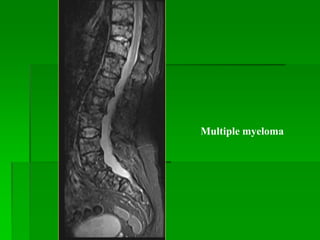

Plasmacytoma và Multiple myeloma

- Plasmacytoma là u đơn độc.

- Multiple myeloma là tổn thương đa ổ, thường gặp ở 50-60 tuổi và

thường gặp nhất ở cột sống (thân sống).

- MRI: tín hiệu thấp hơn tủy xương trên T1W, cao trên T2W. T2FS

giúp xác định độ lan rộng của tổn thương.

Plasmacytoma

MM

Multiple myeloma